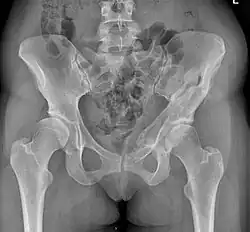

Diagnostik

Sowohl zur genauen Beurteilung der Hüftdysplasie und ihres Schweregrades, als auch zur Planung der Operation werden konventionelle Röntgenbilder des Beckens, sogenannte Beckenübersichtsaufnahmen, angefertigt.

Computertomographien (CT) oder Magnetresonanztomographien (MRT) sind nur in Ausnahmefällen notwendig, um z. B. den Grad der Gelenkschädigung besser beurteilen zu können. Computerverfahren zur dreidimensionalen Darstellung von Organen haben sich im Bereich des Beckens nicht etabliert. Jedoch kommt das 3D-CT des Beckens bei CT-gestützten Navigationsverfahren (siehe unten) zum Einsatz.[7]

Nachbehandlung und Rehabilitation

In den ersten vier bis sechs Wochen liegen die Schwerpunkte der Nachbehandlung in der Mobilisierung des Patienten und ggf. einer Schmerztherapie. Das Bein der betroffenen Seite darf während dieser Zeit nicht oder nur sehr wenig belastet werden. Die Patienten müssen dabei lernen an Unterarmgehstützen oder mittels anderer Gehhilfen zu gehen. Weiterhin übt der Patient unter physiotherapeutischer Anleitung ein, wie er sitzen und aufstehen muss. In den folgenden Wochen wird in einer stationären oder ambulanten Anschlussheilbehandlung die Belastung des betroffenen Beines langsam und stetig aufgebaut, nicht zuletzt um die Muskulatur zu kräftigen. Auch das Treppensteigen und andere alltägliche Bewegungsabläufe müssen in der Zeit bis zum Erreichen der vollen Belastungsfähigkeit neu einstudiert werden. Zur Kontrolle des Heilungsprozesses der Knochen werden in regelmäßigen Abständen weitere Röntgenaufnahmen des Beckens angefertigt.[7] Die Dauer und der detaillierte Ablauf der Nachbehandlung variieren je nach Operateur sowie individuellen Faktoren.